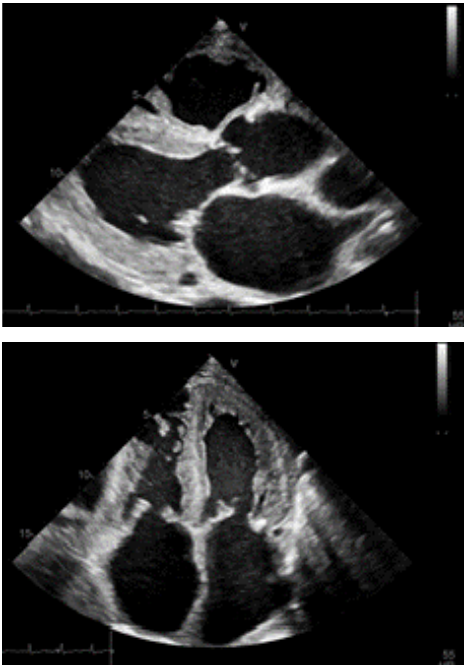

Paciente de 72 anos de idade, sexo masculino, sem histórico de doença coronariana, hipertensão arterial controlada, apresenta síndrome do túnel do carpo, síncope e sintomas de insuficiência cardíaca há 4 meses.

Com base nessa situação hipotética e nas imagens, assinale a alternativa que inclui a principal hipótese diagnóstica e um método complementar de avaliação ecocardiográfica que deve ser aplicado nesse caso.

Imagem: arquivo pessoal.